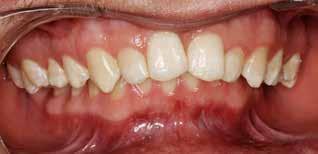

INDRE VÆKSTFORSTYRRELSER I DEN DENTOALVEOLÆRE OG BASALE KÆBERELATION kan almindeligvis kompenseres og korrigeres ved ortodonti og/eller vækstadapterende behandling (1). Imidlertid nødvendiggør ekstreme vækstforstyrrelser i den dentoalveolære og basale kæberelation oftest ortodontisk-kirurgisk behandling involverende forudgående ortodontisk nivellering af tandbuerne og efterfølgende kirurgisk korrektion af de basale kæberelationer ved en Le Fort I-osteotomi og/eller bilateral sagittal splitosteotomi (BSSO) (2). Manglende korrektiv behandling af vækstforstyrrelser i den dentoalveolære og basale kæberelation kan medføre tygge- og bidfunktionelle gener, malokklusion, tvangsføring af mandiblen, trangstilling, psykosociale problemer og uhensigtsmæssigt slid af tænderne (3). Sundhedsstyrelsens specialevejledning har derfor opstillet vejledende kriterier for tilbuddet om kirurgisk korrektion af medfødte og erhvervede kæbeanomalier, når vækstforstyrrelserne i den dentoalveolære og basale kæberelation ikke kan korrigeres ved konventionel ortodontisk behandling alene (4). Disse visitationsretningslinjer kan findes på Dansk Selskab for Oral og Maksillofacial Kirurgis og Foreningen af Specialtandlæger i Ortodontis hjemmesider.

Fig. 1. Klinisk undersøgelse visende et stort horisontalt maksillært overbid kombineret med et dybt bid og bilateralt saksbid på molarerne og præmolarerne.

Fig. 1. Clinical examination revealed a large horizontal maxillary overbite combined with a deep bite and bilateral scissor bite on the molars and premolars.

Betragtelige transverselle okklusionsafvigelser i maksillen behandles almindeligvis med vækstadapterende ortodontisk behandling før begyndelse af vækstspurten, mens kirurgisk korrektion ved en sektioneret Le Fort I-osteotomi eller kirurgisk assisteret ganeekspansion oftest er nødvendig efter afsluttet vækst (3). Transverselle okklusionsafvigelser i mandiblen kan ikke korrigeres ved vækstadapterende ortodontisk behandling som følge af afsluttet vækst i sutura symphysis menti før etårsalderen, hvorfor betragtelige transverselle okklusionsafvigelser oftest korrigeres ved en udvidelse eller komprimering af maksillen (5). Imidlertid er kirurgisk korrektion af betragtelige transverselle okklusionsafvigelser ved en sektioneret Le Fort Iosteotomi eller kirurgisk assisteret ganeekspansion forbundet med stor tendens til recidiv (3), hvorfor transversel udvidelse af mandiblen kan være nødvendig for at mindske recidivtendensen.

Betragtelige transverselle okklusionsafvigelser i den underudviklede mandibel kendetegnes ved en V-formet tandbue, unieller bilateralt saksbid, oral inklinering af molarerne og præmolarerne samt trangstilling i underkæbefronten (6). Mindre transverselle okklusionsafvigelser i mandiblen kan oftest korrigeres ved hjælp af ortodonti alene, mens større transverselle okklusionsafvigelser eventuelt i kombination med andre vækstforstyrrelser i den dentoalveolære og basale kæberelation oftest behandles ved kirurgisk korrektion involverende mandibulær midtlinjeosteotomi eller mandibulær midtlinjedistraktionsosteogenese (MMDO) (6).

Mandibulær midtlinjeosteotomi anvendes almindeligvis ved moderate transverselle okklusionsafvigelser og kan eventuelt kombineres med en bilateral sagittal splitosteotomi, mens mandibulær midtlinjedistraktionsosteogenese udelukkende anvendes ved ekstreme transverselle okklusionsafvigelser og ikke kan kombineres med andre osteotomier på mandiblen.

I nærværende artikel præsenteres et usædvanligt patienttilfælde med en betragtelig transversel okklusionsafvigelse i mandiblen, som blev korrigeret ved ortodonti og mandibulær

Fig. 2. A-C. Panorama, profilrøntgen og CBCT-optagelse viser overensstemmelse med de kliniske fund visende et stort horisontalt maksillært overbid og bilateralt saksbid i sideregionerne.

Fig. 2. A-C. Panoramic x-ray, profile x-ray, and CBCT-image show agreement with the clinical findings showing a large horizontal maxillary overbite and bilateral scissor bite in the lateral regions.

midtlinjedistraktionsosteogenese, og de forskellige distraktionsapparaturer til korrektion af transverselle okklusionsafvigelser i mandiblen diskuteres.

Fig. 3. A. Gennemgående midtlinjeosteotomi svarende til regio 1-1. B. Distraktionsapparatur monteret og fikseret på hver side af osteotomien. C. Panoramaoptagelse under distraktionsfasen. D. Panoramaoptagelser efter distraktionsfasen er afsluttet. E. Intraoperativt klinisk foto efter fjernelse af distraktionsapparaturet, hvor der ses knogledannelse svarende til den tidligere knoglespalte.

Fig. 3. A. Midline osteotomy corresponding to teeth 31 and 41. B. Distraction appliance mounted and fixed on each side of the osteotomy. C. Panoramic x-ray during the distraction phase. D. Panorama recordings after the distraction phase is finished. E. Intraoperative clinical photo after removal of the distractor showing bone formation corresponding to the previous bone gap.